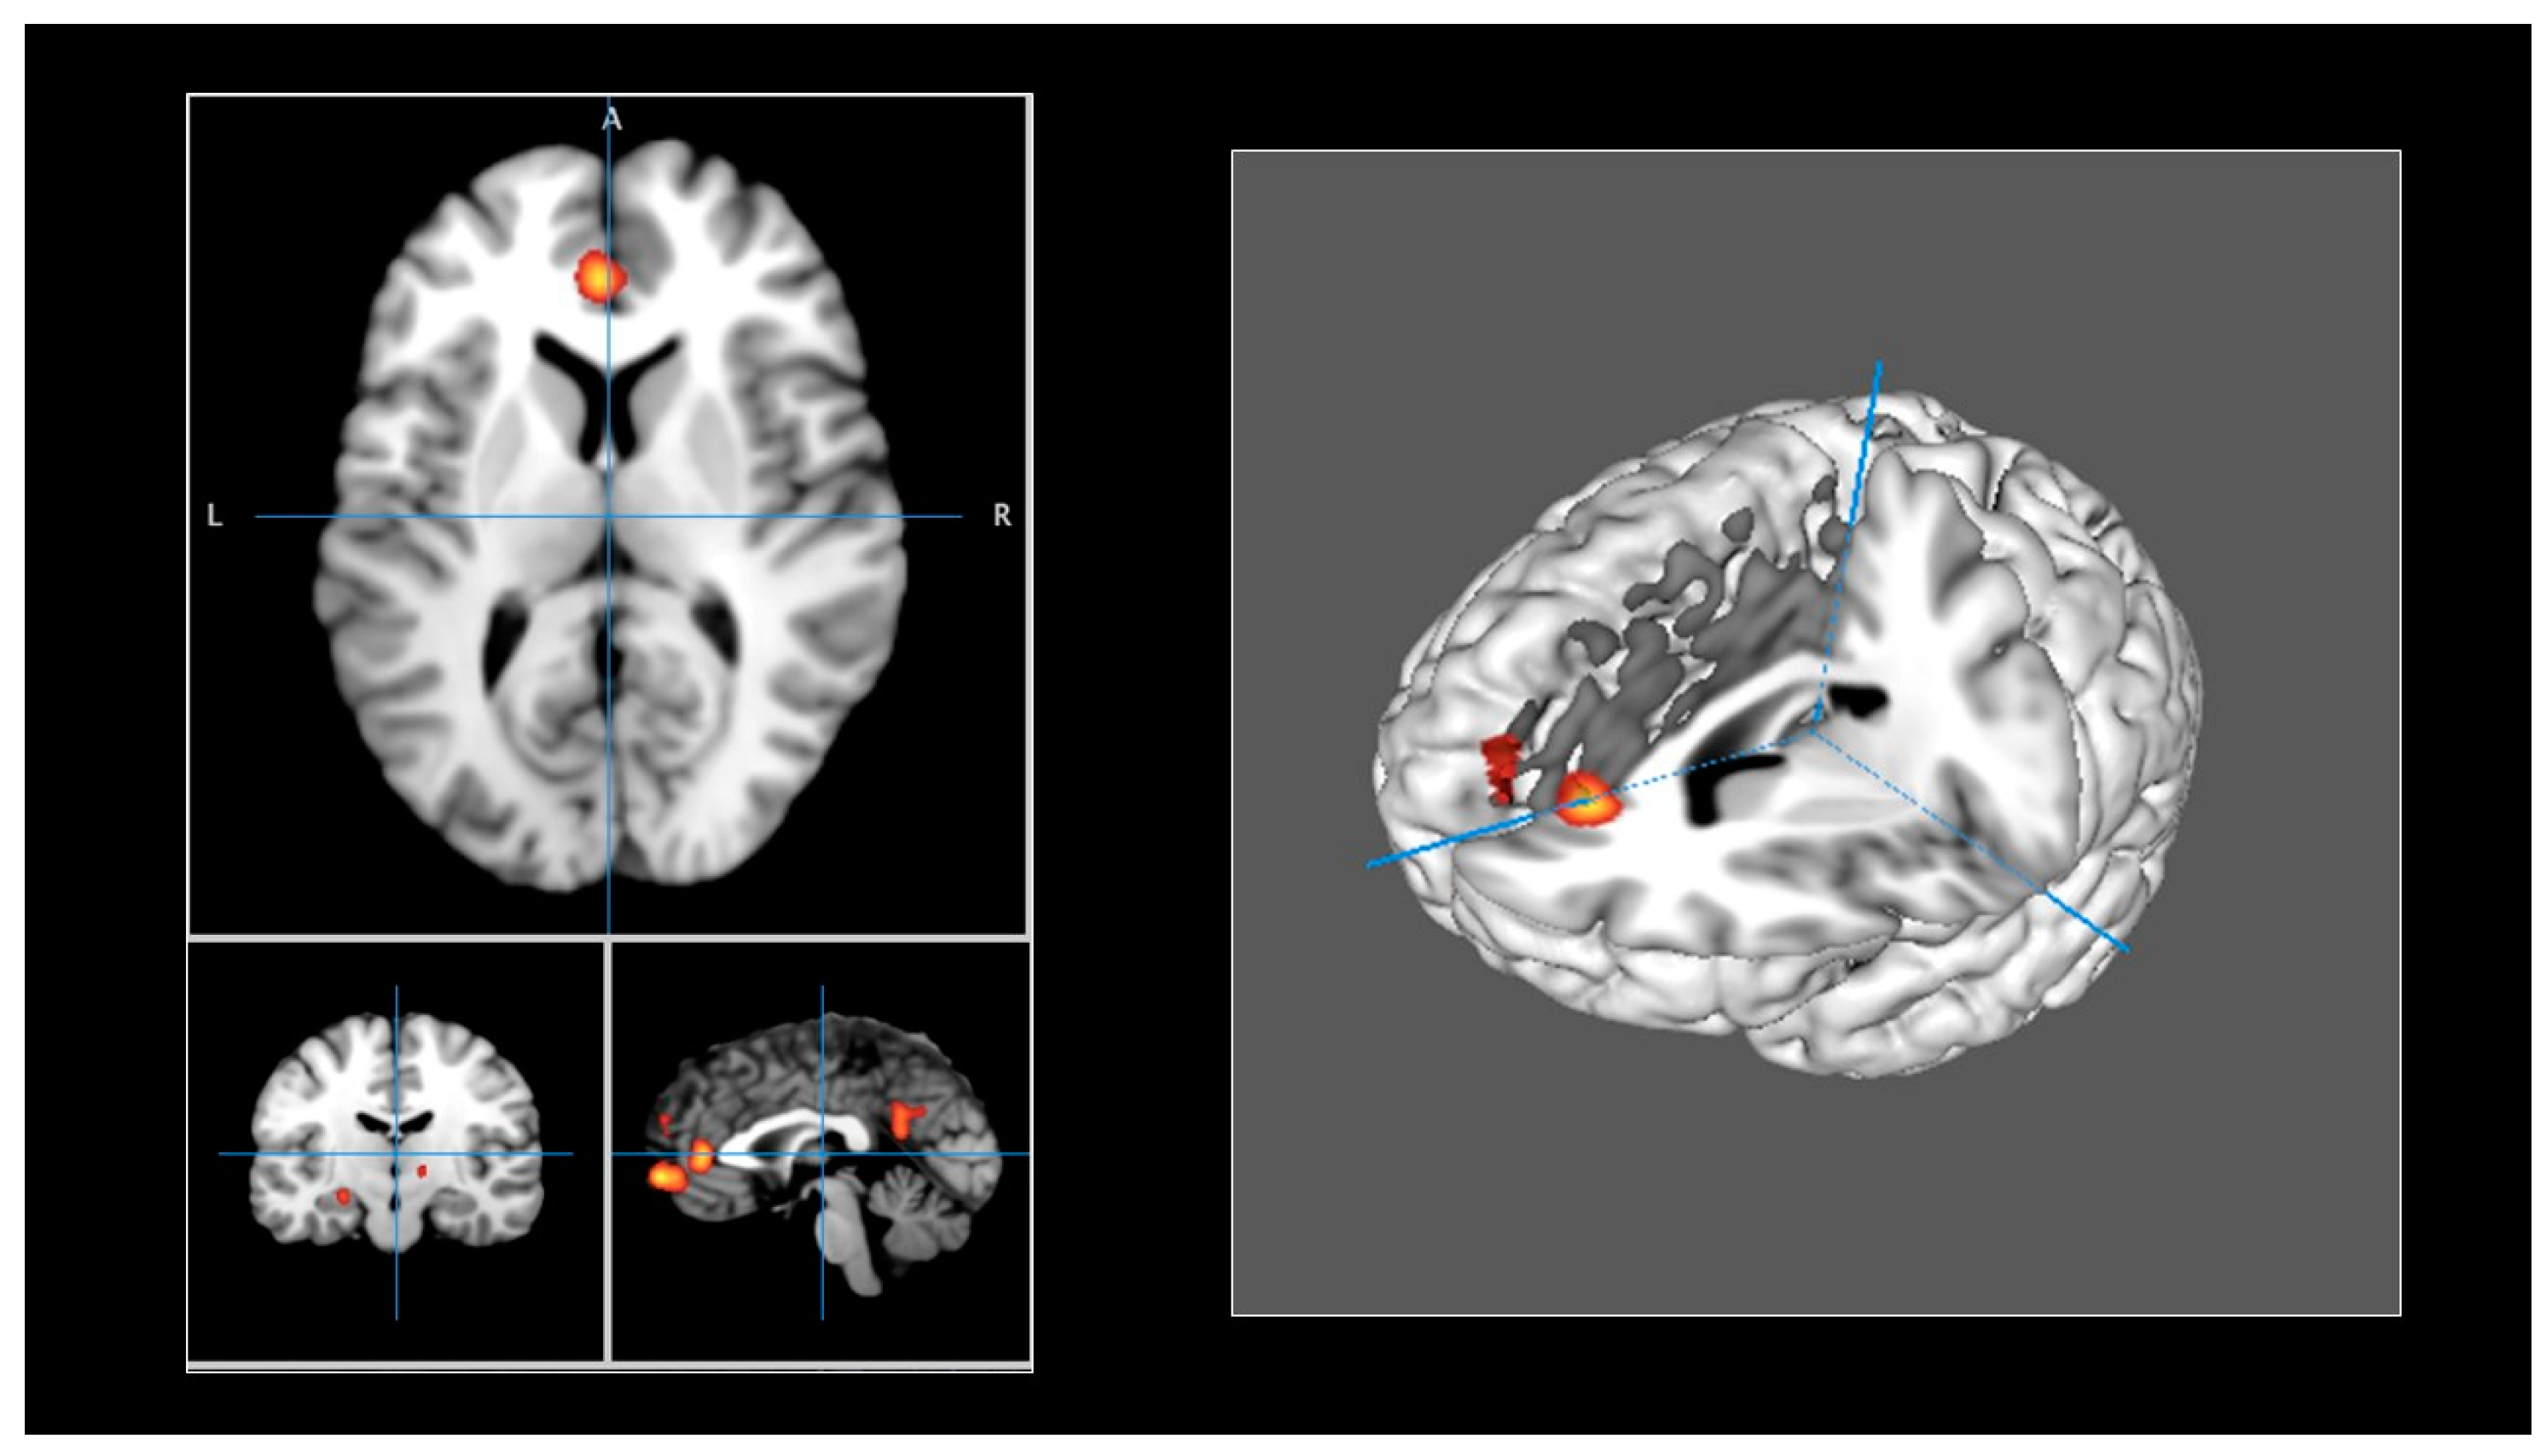

| Cluster | Extrema Value | Side | x | y | z | Label | BA |

|---|---|---|---|---|---|---|---|

| 1 | 0.0217316690 | Left | 0 | 58 | −2 | Medial frontal gyrus | 10 |

| 0.0100130019 | Left | −8 | 40 | 7 | Anterior cingulate | 32 | |

| 0.0117010213 | Left | −2 | 49 | 2 | Medial frontal gyrus | 10 | |

| 2 | 0.0196832641 | Left | −4 | −52 | 20 | Posterior cingulate | 23 |

| 0.0100133905 | Left | −5 | −58 | 15 | Posterior cingulate | 23 | |

| 0.0145051397 | Left | −5 | −53 | 25 | Posterior cingulate | 31 | |

| 3 | 0.0146129345 | Left | −8 | −6 | −6 | Hypothalamus | |

| 0.0100113600 | Left | −13 | −3 | −3 | Medial globus pallidus | ||

| 0.0133150452 | Left | −10 | −5 | −6 | Hypothalamus | ||

| 4 | 0.0119572980 | Left | −2 | 56 | 24 | Superior frontal gyrus | 9 |

| 0.0100121833 | Left | −8 | 56 | 24 | Superior frontal gyrus | 9 | |

| 0.0116624471 | Left | −4 | −57 | 23 | Superior frontal gyrus | 9 | |

| 5 | 0.0149053987 | Left | −30 | −28 | 16 | Parahippocampus | 36 |

| 0.0100117572 | Left | −26 | −25 | −18 | Parahippocampus | 35 | |

| 0.0142512666 | Left | −30 | −26 | −16 | Parahippocampus | 26 | |

| 6 | 0.0134308878 | Left | −24 | −14 | −10 | Hippocampus | |

| 0.0100120860 | Left | −21 | −15 | −9 | Lateral globus pallidus | ||

| 0.0134308878 | Left | −24 | −14 | −10 | Hippocampus | ||

| 7 | 0.0129249868 | Left | −14 | 20 | 47 | Anterior cingulate | 32 |

| 0.0100236097 | Left | −14 | 38 | 2 | Anterior cingulate | 32 | |

| 0.0123331807 | Left | −14 | 41 | 0 | Anterior cingulate | 32 | |

| 8 | 0.0127304997 | Right | 12 | −14 | 0 | Thalamus | |

| 0.0100203901 | Right | 12 | −11 | −1 | Subthalamic nucleus | ||

| 0.0117313978 | Right | 12 | −13 | 1 | Thalamus |